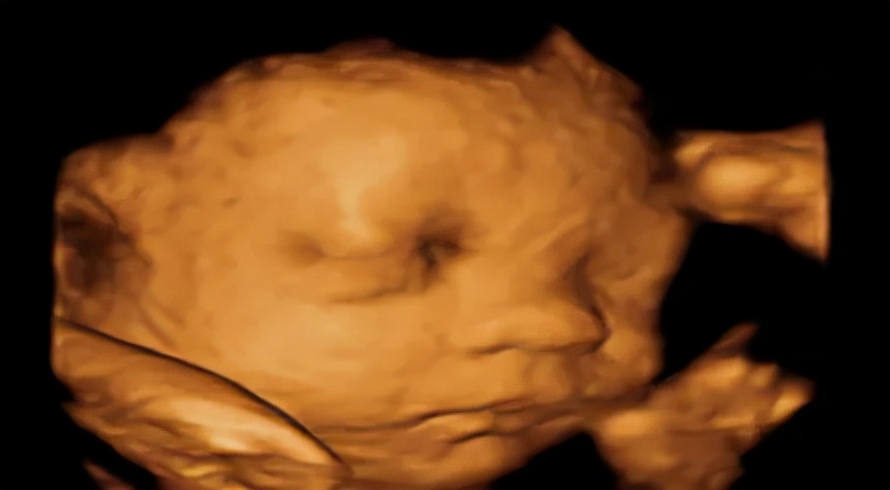

第4次(大排畸):22-24周

这个阶段是看宝宝有身体重大畸形,内脏、头、手指、四肢长骨等均需做细致检查,耗时较长。不需憋尿。这个孕周胎儿结构发育较为完善,可观察到大多数的胎儿畸形。